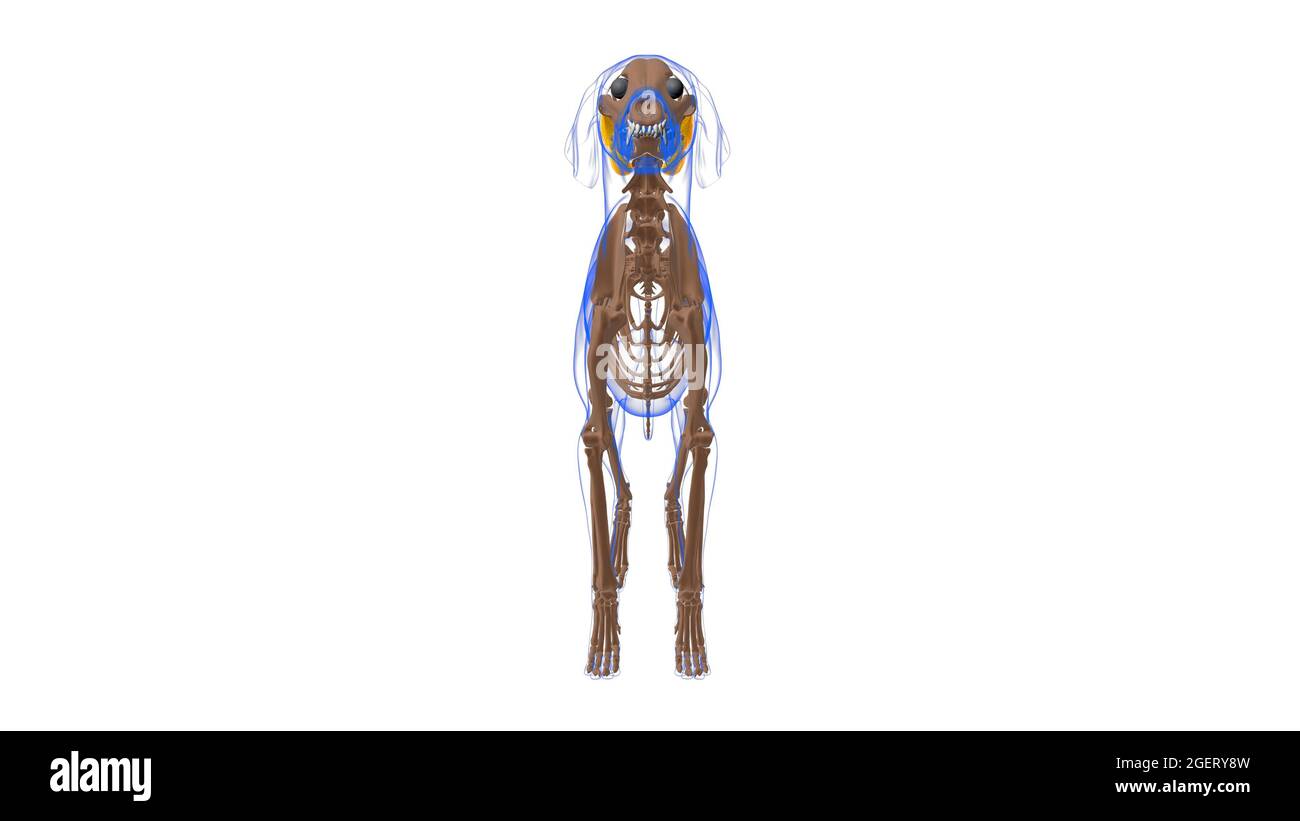

Tensor Fasciae Latae muscle Dog muscle Anatomy For Medical Concept 3D Illustration Stock Photohttps://www.alamy.com/image-license-details/?v=1https://www.alamy.com/tensor-fasciae-latae-muscle-dog-muscle-anatomy-for-medical-concept-3d-illustration-image439390697.html

Tensor Fasciae Latae muscle Dog muscle Anatomy For Medical Concept 3D Illustration Stock Photohttps://www.alamy.com/image-license-details/?v=1https://www.alamy.com/tensor-fasciae-latae-muscle-dog-muscle-anatomy-for-medical-concept-3d-illustration-image439390697.htmlRF2GERY8W–Tensor Fasciae Latae muscle Dog muscle Anatomy For Medical Concept 3D Illustration